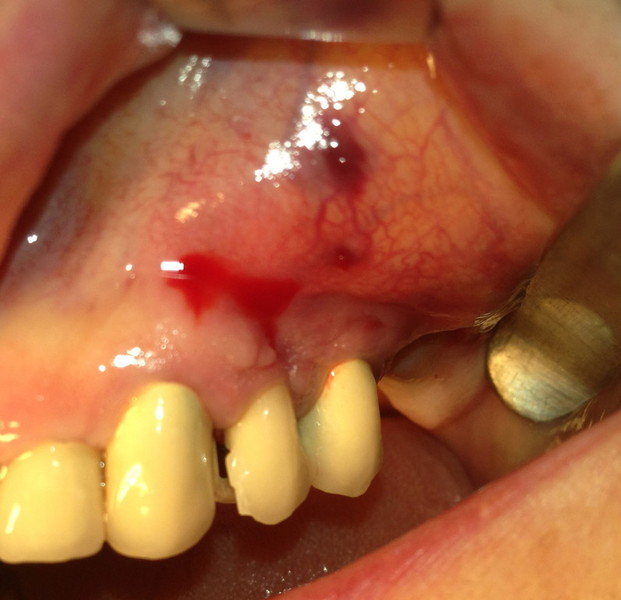

Estrazione radice e inmnesto Epitelio-Connettivale

Rigenerazione difetto parodontale di un canino inferiore con materiale eterologo